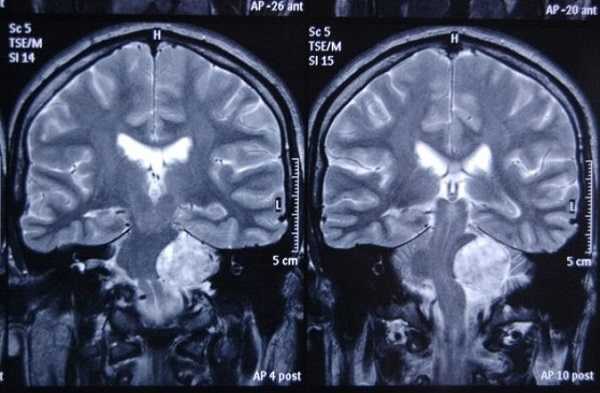

Новообразование в области мосто-мозжечкового угла (фронтальная проекция)